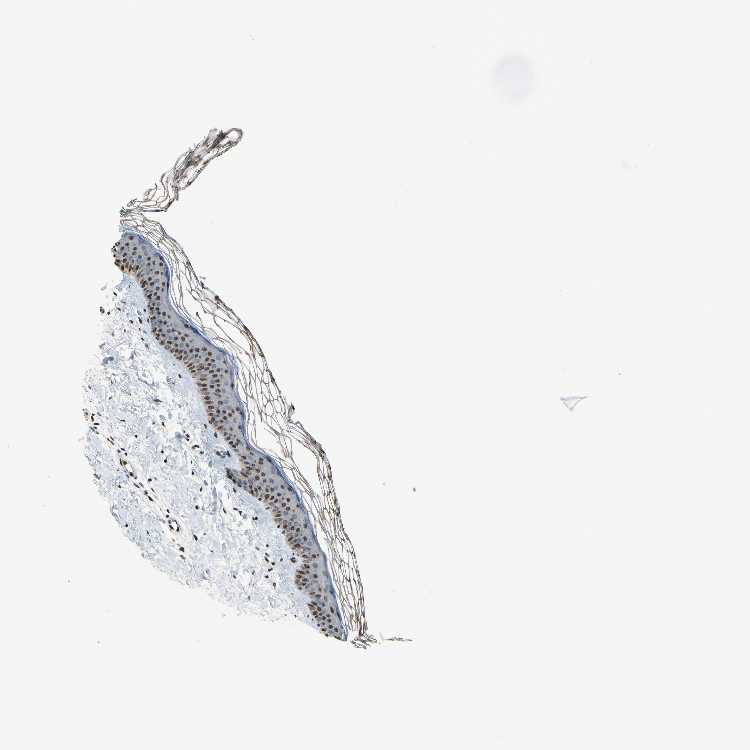

SKIN 1 - Antibody stainingi

Antibody staining in the annotated cell types in the current human tissue is reported as not detected, low, medium, or high, based on conventional immunohistochemistry profiling in selected tissues. This score is based on the combination of the staining intensity and fraction of stained cells.

Each image is clickable and will lead to virtual microscopy that enables deeper exploration of all samples and also displays staining intensity scores, fraction scores and subcellular localization as well as patient and tissue information for each sample.

Antibody HPA007611

Cells in basal layer High

Cells in corneal layer Not detected

Cells in granular layer Medium

Cells in spinous layer High

Endothelial cells High

Extracellular matrix Not detected

Fibrohistiocytic cells High

Langerhans cells High

Lymphocytes High

Melanocytes Low

Vascular mural cells Not detected